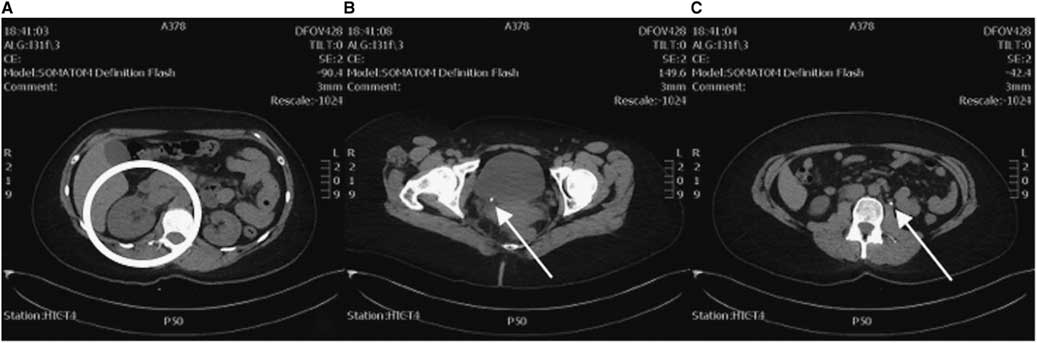

PoCUS revealed right-sided hydronephrosis (Figure 1). Left kidney, bladder, and aorta were all normal. KUB did not reveal calculi in the renal pelvis, ureter, or bladder, but radiology noted that overlying bowel gas and stool obscured a definitive assessment.

Figure 1 Renal imaging with PoCUS. A) Right kidney showing hydronephrosis. B) Left kidney normal comparison.